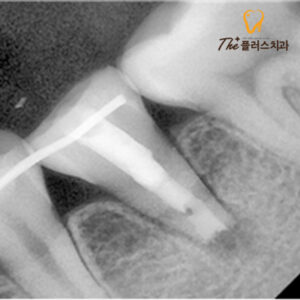

수암동치과 치아재식술의 과정으로는

먼저 치아를 발치한 후 치근 끝을 잘라내고

신경관을 치과 재료인 MTA를 사용하여

충전하게 됩니다.

MTA란 신경을 제거한 뒤 공간을 충전할 때

사용하는 치과용 재료로,

일반 레진 계열 실러의 장점을 살리고

단점은 보완하여 뛰어난 밀폐성을

가지고 있기 때문에 감염을 예방할 수 있고

생체 친화적이며, 통증 감소와 살균 효과,

우수한 치근단 조직 재생 능력이 있습니다.

그 후 염증을 제거하여 본래의 위치에

재식립하게 되는데요.

고정을 위해 옆 치아에

스플린트를 달아 고정해 두었고,

시간이 지남에 따라 치아가 고정되어

잘 아문 모습을 볼 수 있었습니다.